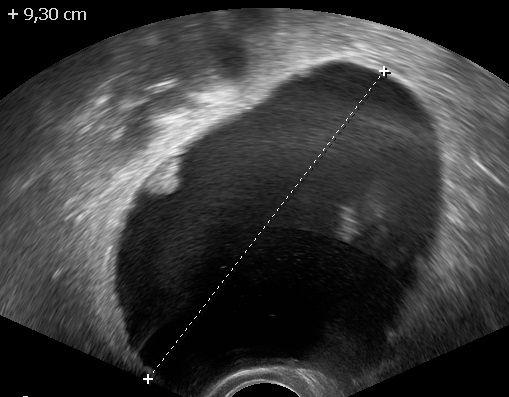

Presence of vascularized and irregular papillary projections in a unilocular cystic mass in the absence of other abnormal findings should arise the suspicion of a borderline ovarian tumor (1, 2, 3). The presence of multiple septa may hint towards a mucinous borderline ovarian tumor (1).

Irregular papillary projection in a unilocular cyst.